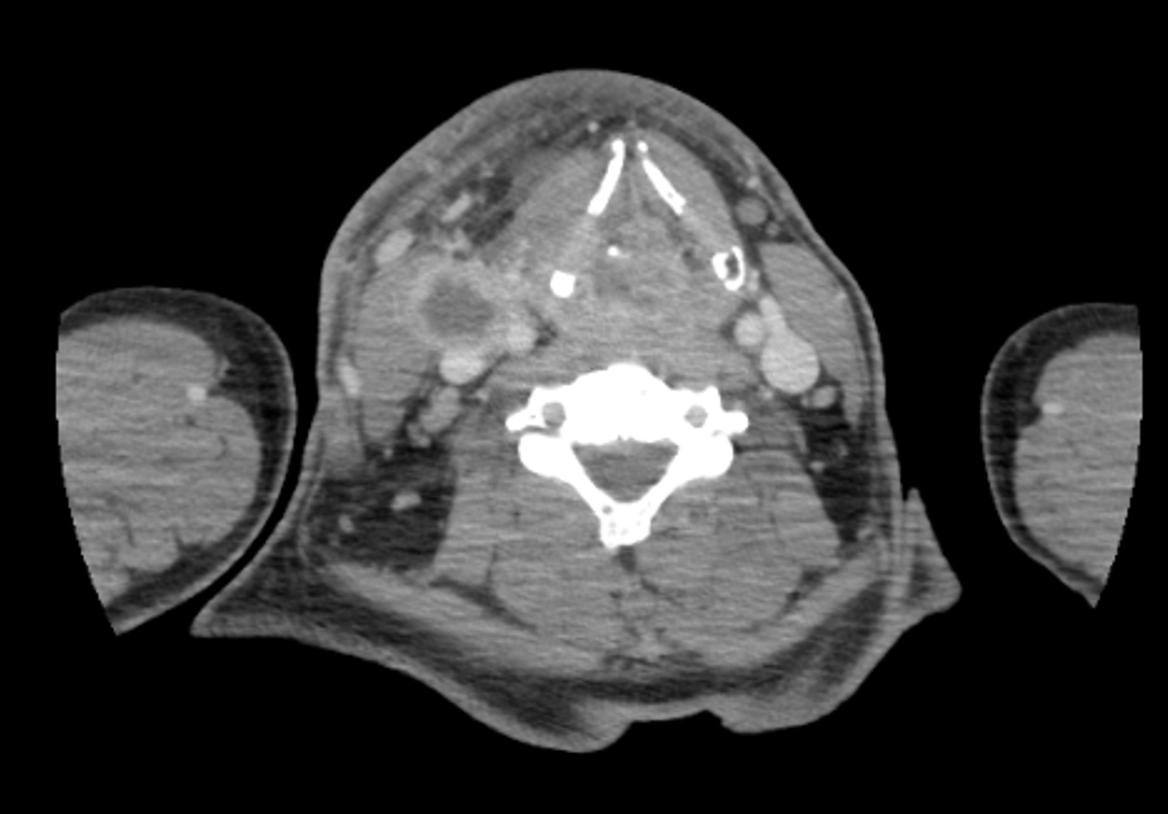

• TDM cervico-thoraco-abdomino-pelvienne (28/07/2025) : masse laryngée hétérogène, mal limitée, de l'os hyoïde à la région thyroïdienne, infiltration locorégionale (épiglotte, segment œsophagien en regard) et lyse bilatérale des lames du cartilage thyroïde. Adénopathies latéro-cervicales droites nécrotiques en logettes, conglomérat d'environ 66 mm en reconstruction coronale. Autres adénomégalies latéro-cervicales bilatérales non remaniées (jusqu'à 11 mm petit axe à droite). Pas d'atteinte suspecte thoraco-abdomino-pelvienne (Fig. 1).

Fig. 1 : TDM cervico-thoraco-abdomino-pelvienne